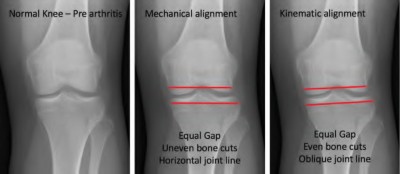

Which of the following statements best describes the surgical principle of true kinematic alignment in total knee arthroplasty?

Explanation